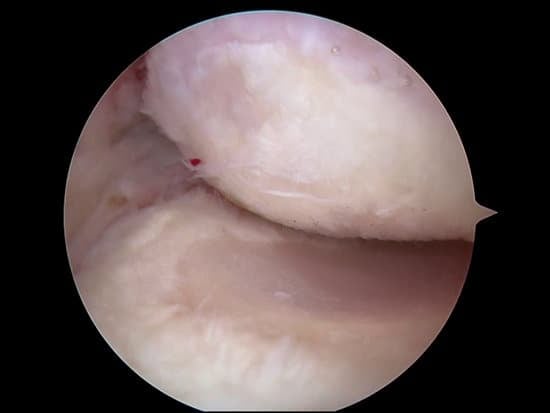

관절경 수술(Arthroscopic Surgery)

작은 절개를 통해 관절 내부의 유착을 제거하고, 손상된 조직을 복원합니다.